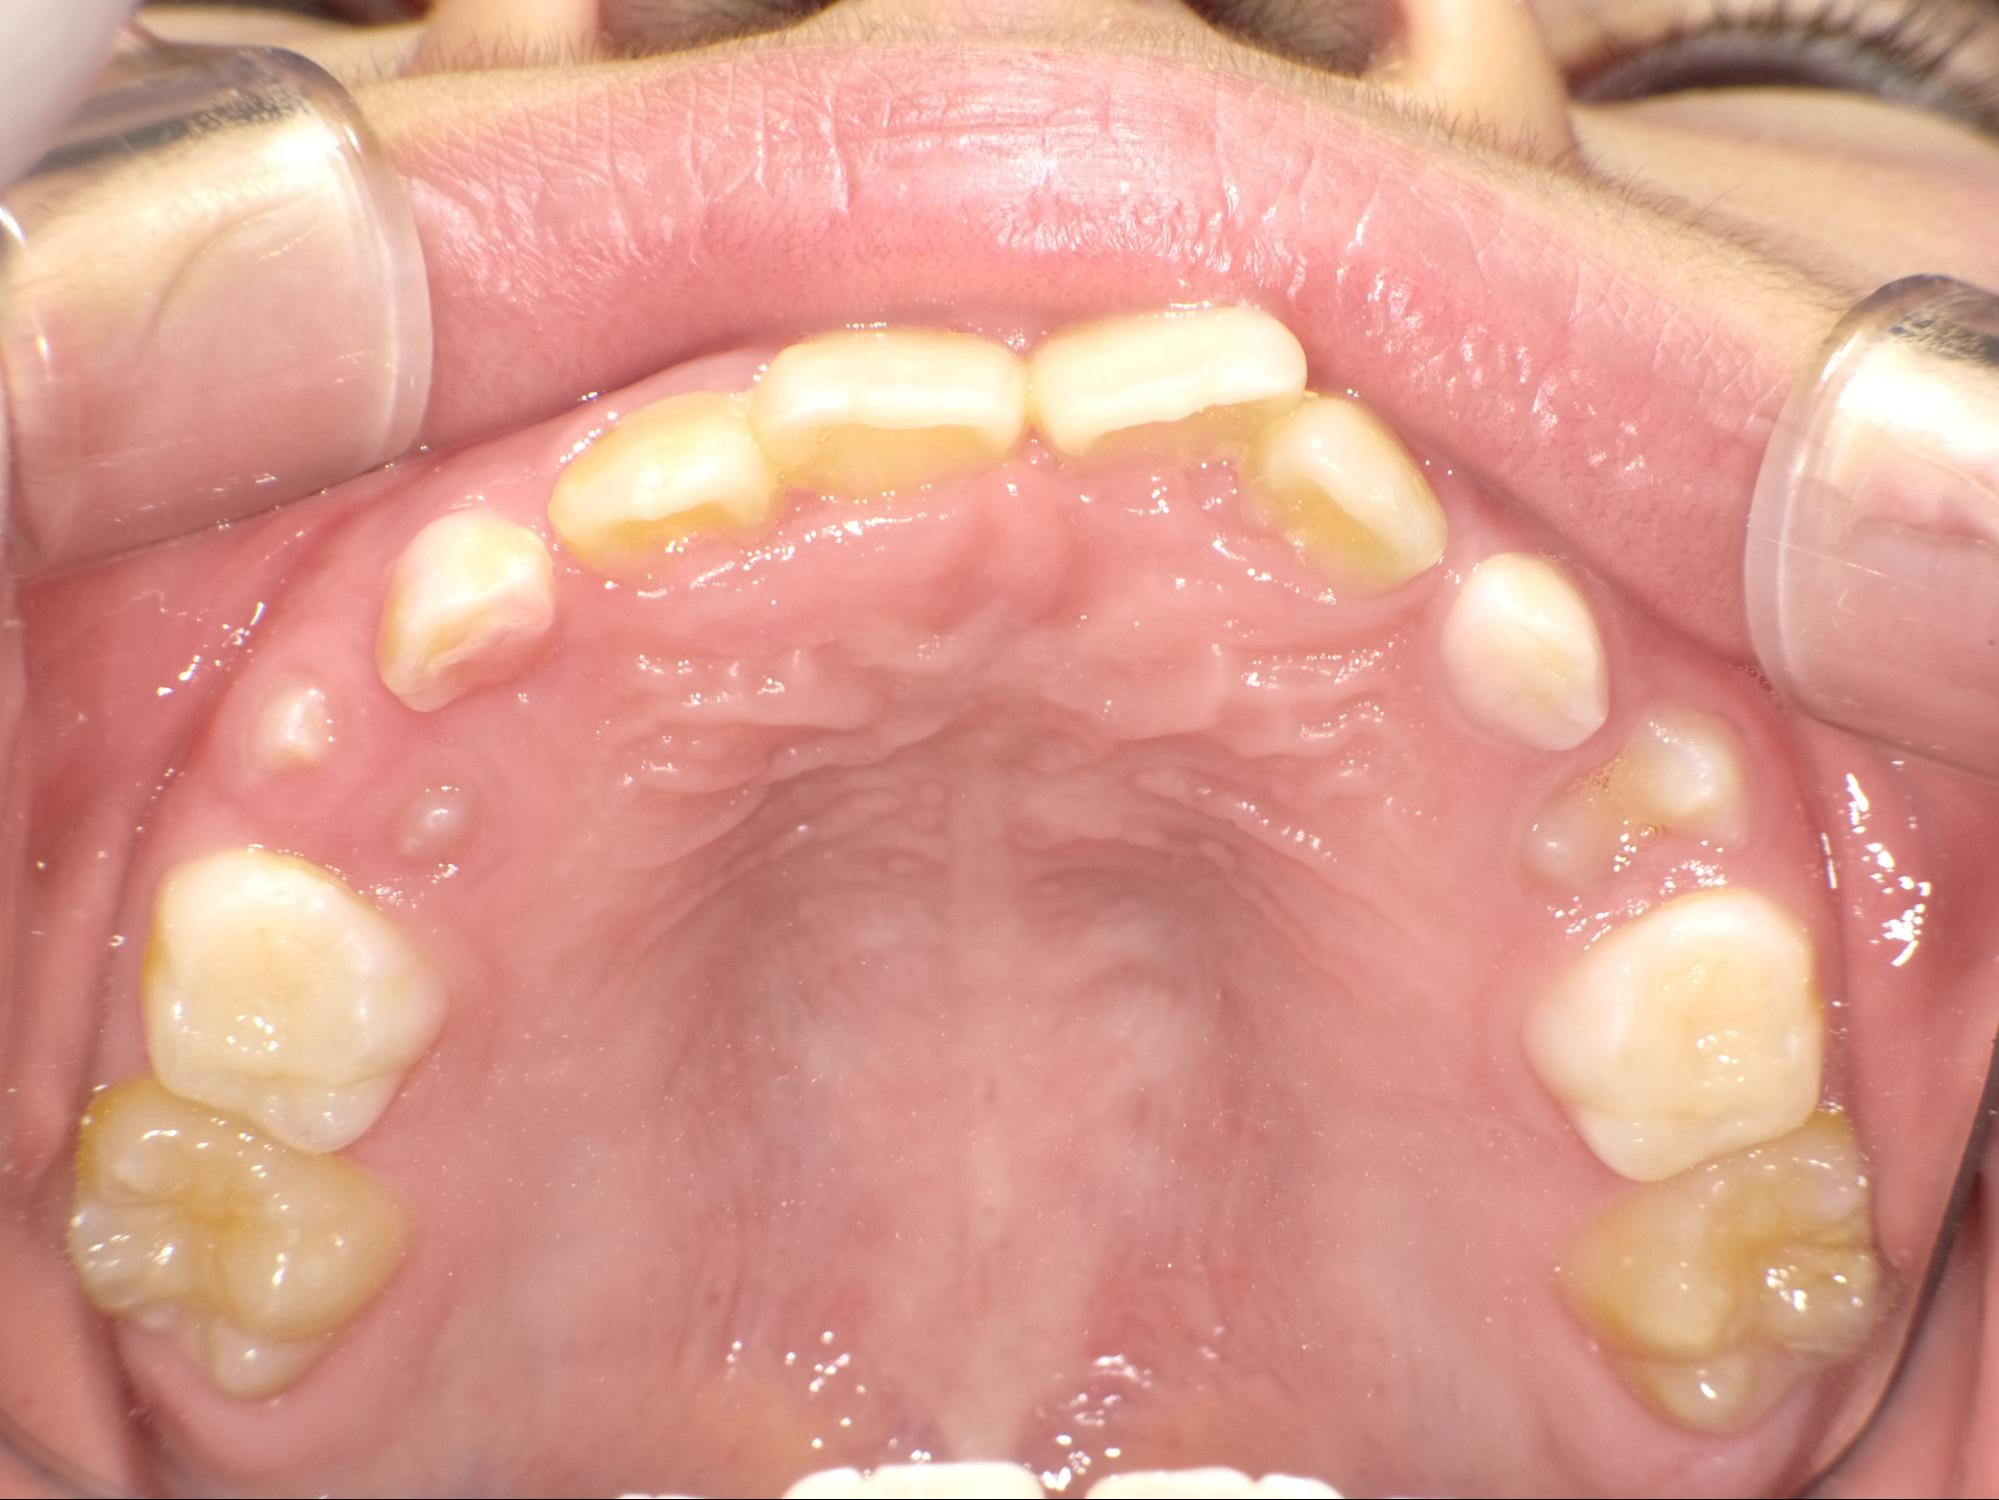

| 年齢・性別 | 7歳1ヶ月の男児 |

|---|---|

| 主訴 | 歯の生えるスペース不足が懸念され、歯列の乱れ(叢生)を整えるために来院された患者様です。 |

| 治療期間・回数 | 1年3ヶ月・11回 |

| 費用 | 420,000円(税別) |